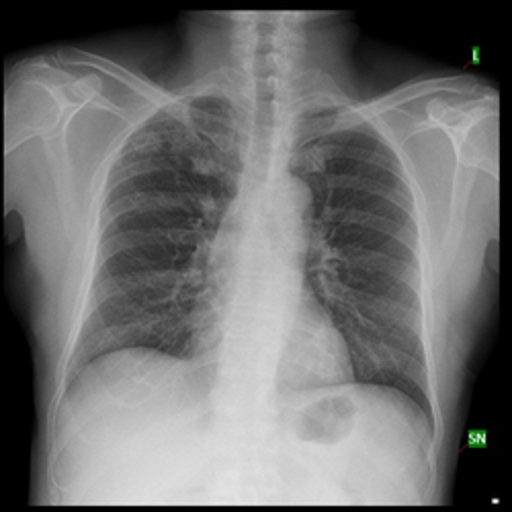

Product Summary SageAI creates a user-centric environment which enables personal account creation and personal health data submission to diagnose diseases. SageAI accepts various inputs, including textual symptoms, self-taken images and biomedical scans. We utilize the BERT model for analyzing textual symptoms, while Imagen aids in processing user-uploaded images in conjunction with BERT. For biomedical scans, BiomedCLIP is used to identify the scan type and pass the scan to a corresponding model. For instance, chest x-rays are distinguished by the BiomedCLIP model from other types of biomedical scans and then passed into the ResNet-152 model to diagnose diseases.

SageAI leverages AI models to deliver swift, cost-effective, and globally accessible disease diagnoses, emphasizing inclusivity through its advanced features. Currently, SageAI focuses on diagnosing diseases through chest x-rays, with plans to extend its diagnostics to include CT and MRI scans for wider coverage.